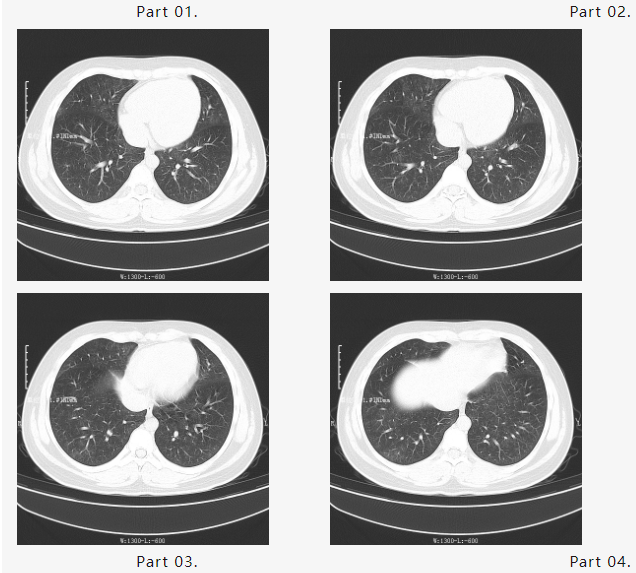

根据以往救治经验,钱源及团队开展多次对症治疗,效果并未凸显。随即再更改治疗方案,结合新病例的治疗特点及用药方式,采用量化治疗疗法。经过几天的精心治疗和护理,小毛终于转危为安,胸闷气急的症状逐渐消失,肺从“一片白茫茫”变为“一丝一缕的白”症状明显好转,复查了第一次胸部CT,结果显示如下:

在大家的不懈努力下,短时间内“白肺”明显吸收好转。马博激动又兴奋地告知大家这个好消息,大家不约而同打开小毛胸部CT片反复阅览,均露出久违的笑容……